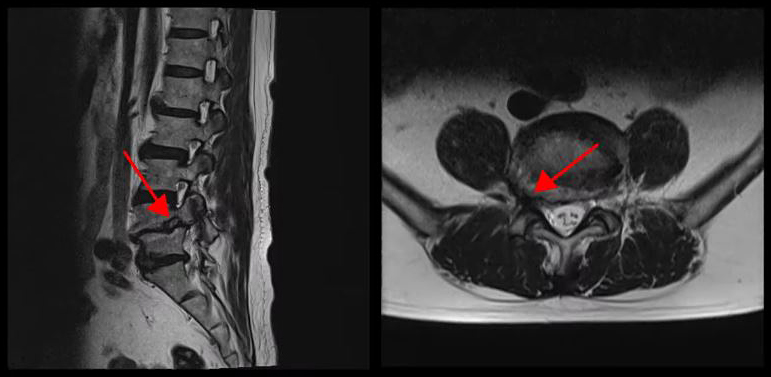

<5-1번 디스크 파열>

이 환자분의 허리 MRI를 보면 4번, 5번 오른쪽에 심한 추간공협착증과 2단계의 척추전방전위증이 있는데, 특히 척추전방전위증 때문에 추간공이 많이 좁아져 있는 상태입니다. 또 왼쪽의 다른 마디에 디스크 파열이 있으나 환자분이 왼쪽으로는 증상이 전혀 없는 것으로 보아 이 디스크 파열은 통증을 일으키지 않는 무증상의 디스크 파열입니다.

이렇듯 4번, 5번 마디의 심한 추간공협착증과 척추전방전위증으로 인해 이 환자분은 다리에 마비가 왔고, 발목에 힘이 빠져 거의 걷지 못하는 상태였습니다. 새벽에 잠에서 깨 화장실을 갈 때는 네 발로 기어갈 정도로 증상이 심했습니다. 신경주사도 많이 맞아봤지만 통증이 전혀 줄지 않아서 결국 수술을 결심하셨는데요. 대학병원을 비롯해 정형외과 및 신경외과 등 아홉 군데 병원에서 진료를 받았지만, 어려운 수술이라고 말하면서 척추유합술, 감압술 등 병원마다 제시하는 수술방법이 다 달라 큰 혼란을 겪으셨습니다. 게다가 수술 후 후유증이나 잔존 증상에 대한 물음에 ‘있을 수도 있고 없을 수도 있다’라는 의사의 말에 수술을 고민하던 중 마지막이라는 생각으로 저희 모커리에 내원하셨습니다.

이 환자분처럼 상태가 매우 심각한 중증 협착증, 2단계 이상의 척추전방전위증도 허리 주변 근육의 기능을 회복하고, 문제를 해결해주는 근육재활치료를 통해 수술 없이 충분히 치료가 가능합니다.

그 이유는 척추관이 매우 심하게 좁아졌거나, 또는 척추 뼈가 많이 밀려나갔어도 허리 주변 근육의 상태가 좋고, 근육이 제 기능을 잘하고 있으면 통증이 없거나 통증이 훨씬 덜합니다. 그래서 허리 주변 근육의 기능을 회복시키는 근육재활치료를 잘해주면 척추전방전위증, 협착증 증상이 많이 좋아질 수 있는 것입니다.